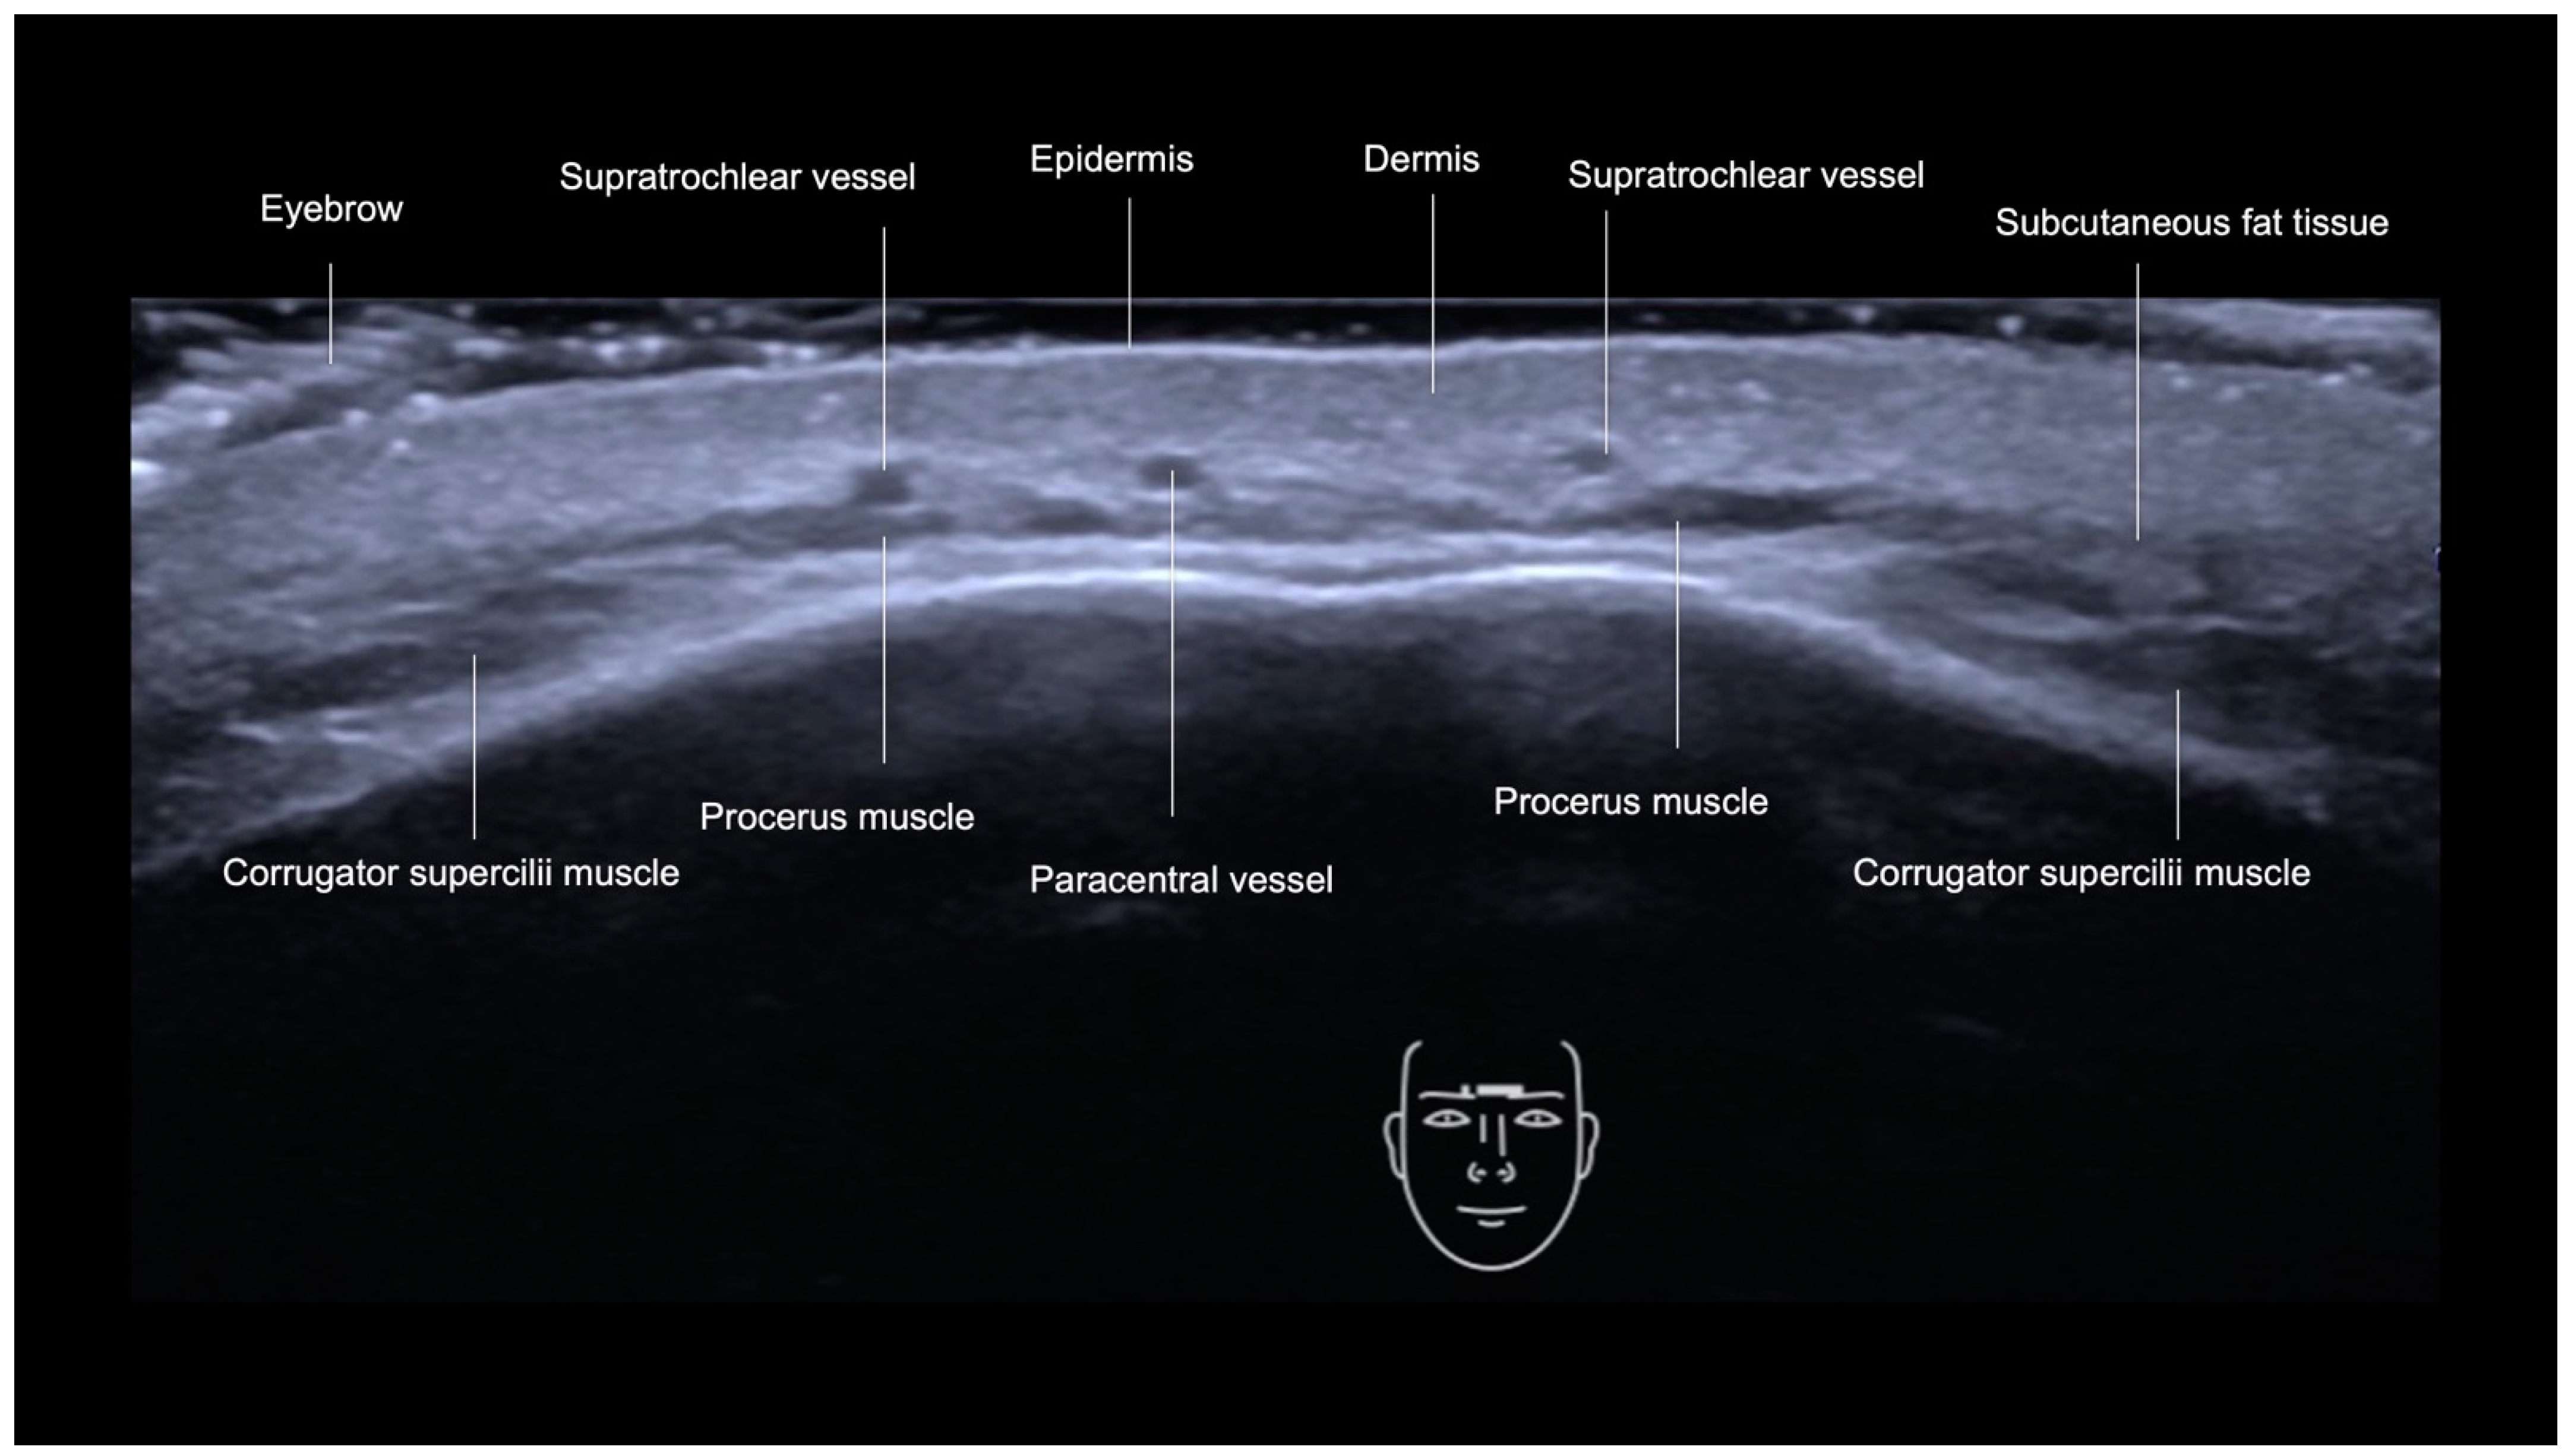

Glabella

- Epidermis: a hyperechoic line.

- Upper dermis: a hypoechoic homogeneous layer.

- Lower dermis: a hyperechoic layer.

- Subcutaneous fat tissue: a hypoechoic layer composed of fat lobules and hyperechoic septae.

- Suprafrontalis fascia: a thin hyperechoic upper layer of galea aponeurotica.

- Frontalis muscle: a hypoechoic band-like structure.

- Retro-Orbicularis Oculi Fat compartment (ROOF): a hyperechoic fibrous fat layer that separates the frontalis muscle from the bone. It can be appreciated in the inferolateral part of the forehead.

- Periosteum and subfrontalis fascia: a hyperechoic line showing combined imaging of these structures, with acoustic shadowing below. Due to the convexity and reflective nature of the frontal bone, there is usually a mirror imaging artefact.